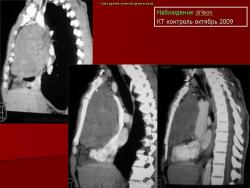

НАБЛЮДЕНИЯ КОЛЛЕГ

1.

2.